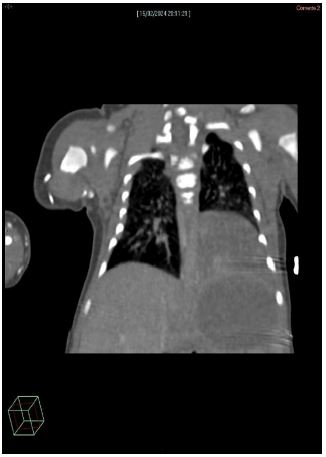

Due to the good clinical conditions, we started a LUS follow-up. At one month of life a CT scan confirmed the pulmonary malformation: an extralobar pulmonary sequestration with abnormal vessel from the thoracic aorta and venous drainage in azygos and emiazygos veins was identified in the lower pulmonary left lobe (Figure 2).

Figure 2: CT scan: At the left basal lobe, a triangular parenchymal consolidation area without continuity with the tracheobronchial tree or the main pulmonary arterial and venous structures. After contrast administration, the venous drainage is identified in the azygos-hemiazygos venous system and arterial vascularization is ensured by a small vessel originating from the descending thoracic aorta.